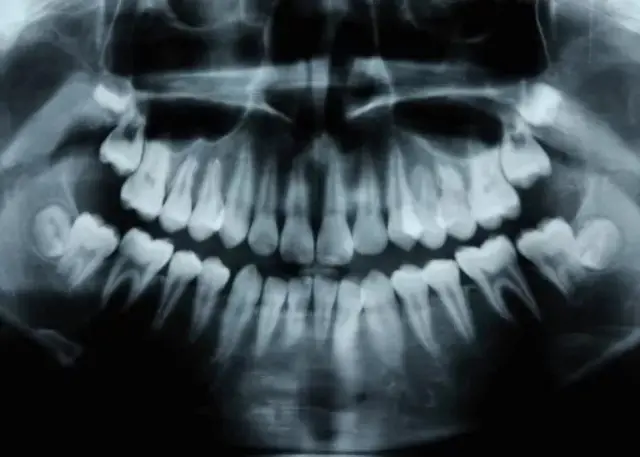

Entassées, mal alignées, criblées de caries et de gencives enflammées, nos dents sont tristement célèbres pour leurs défauts.

La parodontite, ou maladie des gencives, est la deuxième maladie buccale la plus répandue après la carie dentaire. Elle touche plus de 47 % des adultes de plus de 30 ans.

Après 65 ans, 64 % ont une parodontite modérée ou sévère. À l'échelle mondiale, il s'agit de la onzième maladie la plus répandue dans le monde.

La parodontite est une infection qui ne se situe pas à la surface des gencives que vous pouvez voir lorsque vous souriez, mais en profondeur.

Après une phase initiale d'inflammation superficielle dans la partie visible de la gencive (gingivite), les bactéries descendent sous le rebord gingival dans des poches situées près de la racine de la dent où elles érodent les structures qui maintiennent la dent en place.

En raison de la nature cachée de la parodontite, de nombreuses personnes qui en souffrent ne savent pas qu'elles en sont atteintes avant d'avoir atteint un stade très avancé. Cette maladie a une composante génétique et est également influencée par l'hygiène bucco-dentaire.